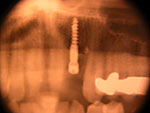

Frontzahn-Implantation: